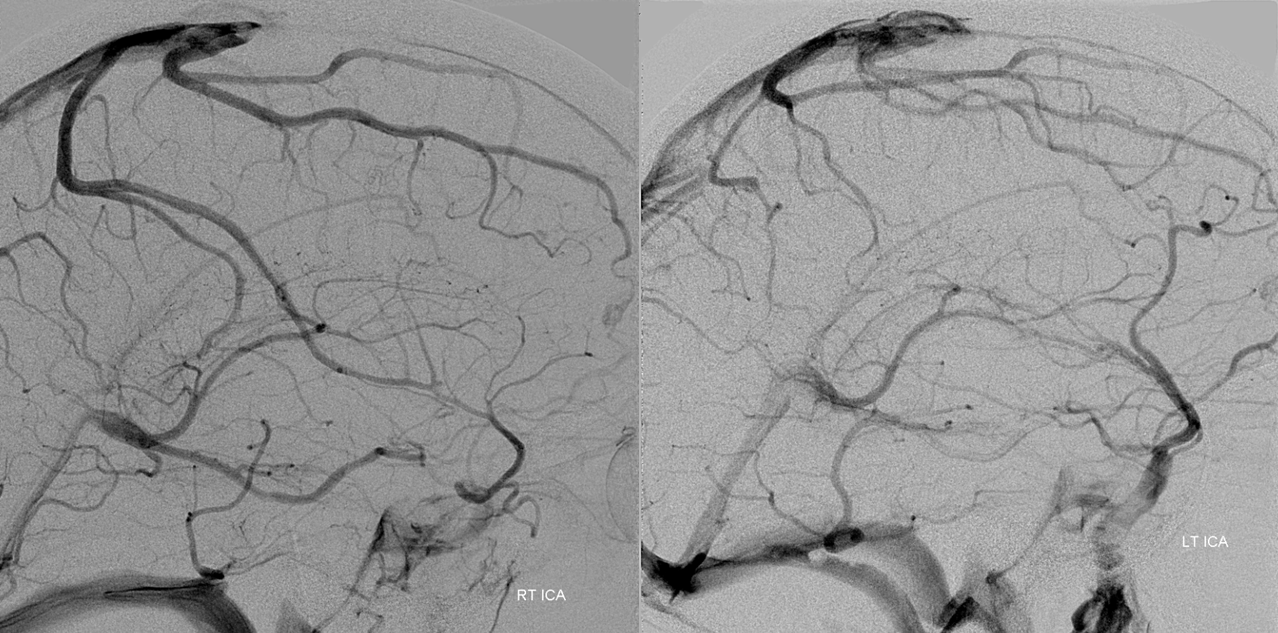

All of the above anatomic knowledge can become very useful in evaluation of venous thrombosis. Numerous collateral pathways develop in this setting attempting to compensate for the loss. The most dramatic cases usually involve the largest channel — the superior sagittal sinus. In this case, a man presented with what initially was thought to be vasculitis-related brain hemorrhage. Subsequent workup led to an angiogram, where sagittal sinus thrombosis with extensive trans-cerebral and trans-osseous emissary vein collateral channels was seen. In retrospect, these findings were present on the patient’s earlier contrast MRI. “Venovibe” or other contrast-enhanced MR venograms can very sensitive, particularly when interpreted with the appropriate index of suspicion. Noncontrast 2-D time of flight MRV I consider to be next to useless as a problem-solving technique. Any thin-slice postcontrast T1 study is vastly superior.